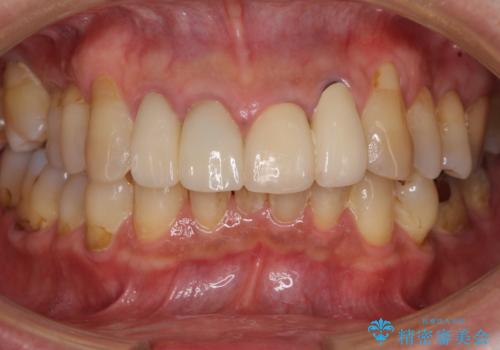

根管治療を実施した後、オールセラミッククラウンに補綴することとしました。

前歯のセラミッククラウンを装着したばかりであったので、根管治療のためにクラウンを壊さなければならないことを残念に思っていらっしゃいました。

しかし、根管治療後はすぐに痛みがひき、治療を受けられて良かったとのことでした。